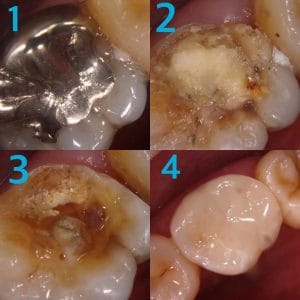

銀歯の中にできた虫歯の症例です。

「痛くないから今は虫歯がない」と話す方がいらっしゃいますが、それは大きな間違いです。

大人になってからの虫歯は痛みが出ることの方が圧倒的に少なく、口の中の病気は基本的に自覚症状と病気の重さが比例しません。

全ての銀歯の中に虫歯があるわけではありませんが、以下の理由から虫歯には注意が必要です。

1.銀歯はかけたり割れたりすることは絶対にないが、力がかかると”たわむ”

→ゆえに汚れが隙間に入りやすい

2.接着剤がつきやすいので、取れずらい

→ゆえに汚れもつきやすい

この症例のように、自覚症状が無くても銀歯を外してみたら大きな虫歯があるというケースも少なくありません。

しっかり検査、診断してくれるクリニックに定期的に行くことをおすすめいたします。